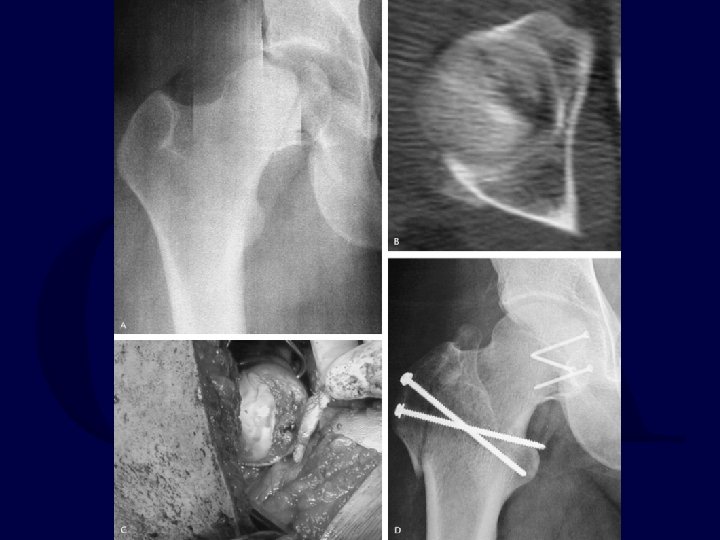

2. Hip Dislocation with Femoral Neck Fracture Usually the dislocation is posterior. Thus, Kocher-Langenbeck approach. If fracture is non-displaced, stabilize fracture with parallel lag screws first. If fracture is displaced, open reduction of femoral head into acetabulum, reduction of femoral neck fracture, and stabilization of femoral neck fracture.

Pipkin Classification I Fracture inferior to fovea II Fracture superior to fovea III Fracture of femoral head with fracture of femoral neck IV Fracture of femoral head with acetabulum fracture

Pipkin II AO/OTA 31 -C 1. 3

Pipkin III • Femoral head fracture with femoral neck fracture.

Pipkin IV • Femoral head fracture with acetabulum fracture. • High incidence of post-traumatic AVN.

Pipkin III Fractures High incidence of AVN and degeneration with displaced fractures. – Relative indication for hemiarthroplasty in older patient due to this risk – Attempt at ORIF warranted in active, younger patients If femoral neck fracture is non-displaced, do not attempt manipulative reduction of hip until femoral neck is stabilized.

Femoral Head Fracture-Dislocation with Displaced Femoral Neck Fracture • Closed reduction attempts are futile. • ORIF in young: open reduction of hip, then reduction and stabilization of femoral neck and head. • Arthroplasty in middle-aged and elderly (No good results with ORIF reported in literature).

Femoral Head Fracture-Dislocation with Non-Displaced Femoral Neck Fracture Must consider stabilizing femoral neck fracture before performing reduction of hip.